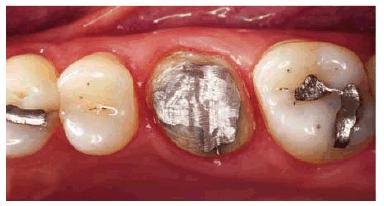

Principles for Crown Preparation

The proper preparation of the tooth after completion of the post and core

restoration is very important. Even with the ideal canal preparation and post

restoration, the post has a tremendous potential to act as a wedge in the tooth

root. This can result in initiation of a vertical root fracture and subsequent

loss of the tooth. The best way to protect the tooth (ie, the root) against

this wedging force is by the creation of a ferrule design in the crown

preparation on the tooth.3,16,18,21,28 The ferrule design is the

encirclement of 1 to 2 mm of vertical tooth structure by the crown. This

encirclement, like metal bands on a barrel, helps protect the tooth from

fracture. It resists the wedging forces that would be transmitted to the post

from the occlusion. To create an adequate ferrule, the margin usually must be

prepared further apical. Often, this requires a crown-lengthening procedure to

gain sufficient tooth length to prepare the ferrule (Figur 323s1823d e 18-19). This principle of creating a

ferrule around the tooth is probably the single most important principle in the

restoration of endodontically treated teeth (Figur 323s1823d es 18-20A 18-20B, and 18-20C). If an adequate ferrule is

obtained, the type, material, and design of the post and core become much less

important. Conversely, if a ferrule is not obtained, then the tooth is at risk

of fracturing no matter what type of post and core is used. This is especially

true for teeth that are expected to carry a heavy load such as a removable

partial denture or fixed partial denture abutment or in patients who exhibit

excessive wear or bruxism.

Figur 323s1823d e 18-19: Ferrule design resists wedging force of post.

Figur 323s1823d e 18-20A: Proper ferrule design on preparation for porcelain-fused-to-metal crown.

Figur 323s1823d e 18-20B: Radiograph showing cast post and core after cementation. Note that the post is more than one-third of the diameter of the root at the cement-enamel junction and is tapered. Tooth preparation did not exhibit ferrule design.

Figur 323s1823d e 18-20C: Same clinical case as in Figur 323s1823d e 18-20B after 8 years. Note the oblique root fracture. Such a fracture could be prevented by a more conservative post in combination with proper ferrule design in the crown preparation.